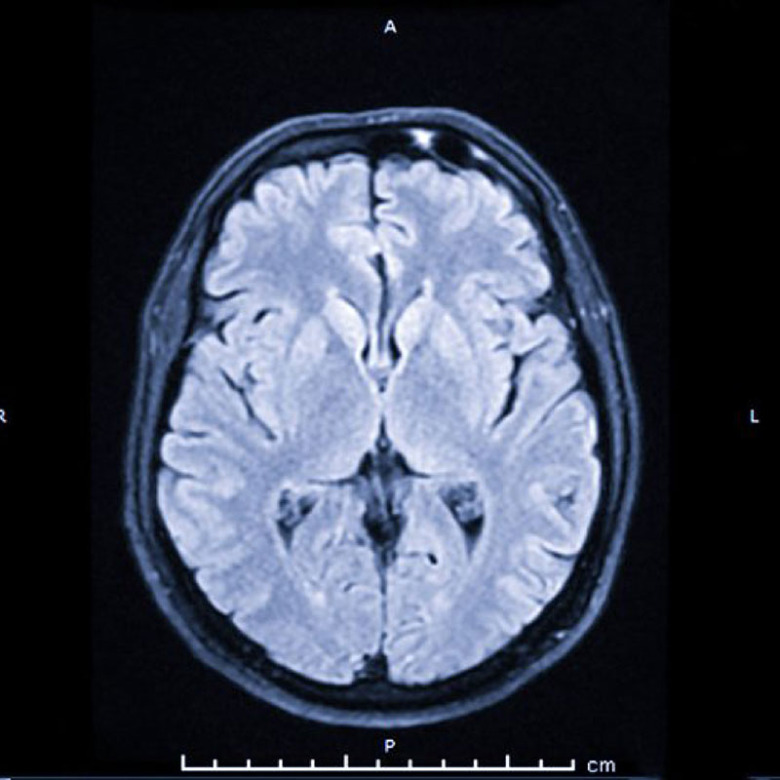

Fler användningsområden hela tiden Dagens magnetkameror är kraftfulla med detaljrik upplösning. De används till en stor mängd undersökningar, allt från skador på skelett till cancer och sjukdomar som påverkar blodflöden i kärl och hjärta. Även funktioner i hjärnan kan registreras, som beroenden och depression. Användningsområdena utvidgas och förbättras för varje år